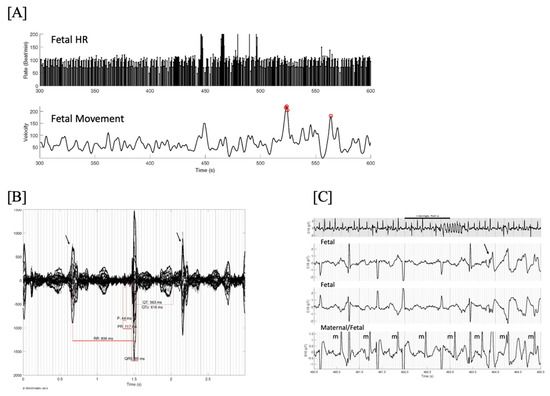

- Short VA SVT (Figure 3 and Figure 4) demonstrates a ventricular–atrial (VA) interval that is less than half of the ventricular–ventricular (VV) interval (VA:AV ratio < 1) and a sudden onset and termination of tachycardia; tachycardia usually terminates with a non-conducted atrial contraction. Short VA SVT includes AVRT (also known as orthodromic reciprocating tachycardia, ORT) and atrioventricular nodal reentrant tachycardia (AVNRT). Short VA SVT typically presents after 18 weeks of gestation.

- Long VA SVT (Figure 4) demonstrates a VA interval that is more than half of the VV interval (VA:AV ratio > 1). Long VA SVT includes EAT and PJRT. A distinguishing feature of EAT is tachycardia termination with ventricular contraction. Long VA SVT may occur as early as 12 weeks of gestation. Because long VA tachycardias have slower rates, they are less likely to cause hydrops.